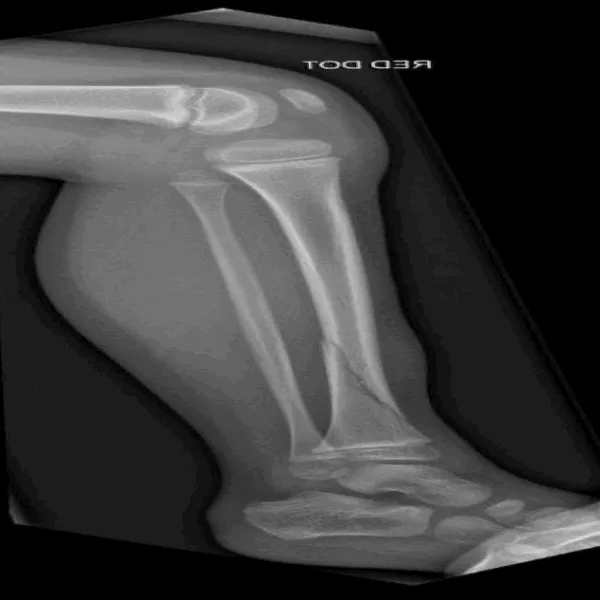

7. HBFMID 人体骨折图像数据集

HBFMID 是一个医学影像数据集,旨在为骨折检测与分类任务提供支持。该数据集融合了多模态影像、覆盖多部位、多样显示形式,并进行了充分增强和明确划分,适用于训练和评估骨折检测与分类模型,尤其在医学图像分析与深度学习研究中具有较高价值。

直接使用:https://go.hyper.ai/IPIOE

数据集示例